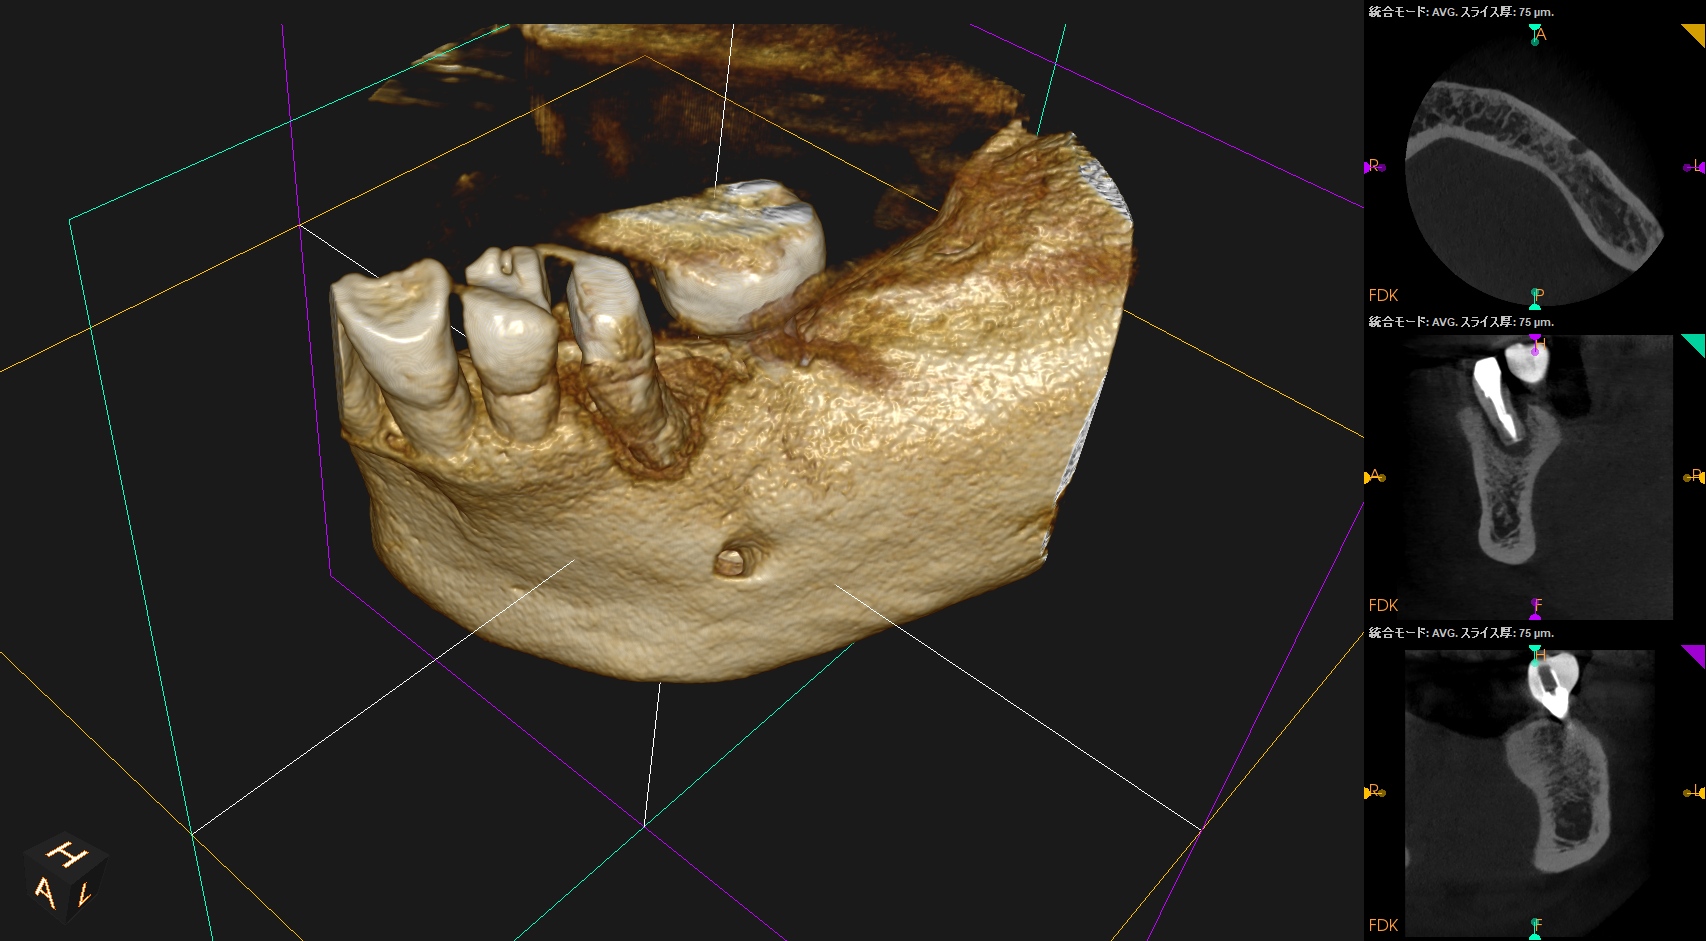

#20の周囲には歯槽骨がほぼないので容易に抜歯ができた。

メチレンブルーで染め出したがVRF所見はなかった。

再植する前にLight testをしたが破折所見はなかった。

抜歯窩を生食で洗浄し、再植した。

術後にPA, CBCTを撮影した。

長いスクリューピンの除去には約50分かかったがIntentional Replantationは15分で終了した。